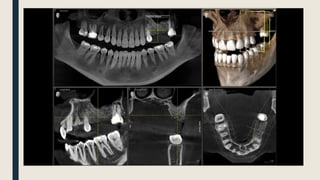

CBCT Images:

• Normally, you will have 5 different views

for any image you take

• The 3D model does not have any medical

indication as it is used for demonstration

uses only

• The 2D panorama is created as a result of

adjusting the jaw line of the 3 anatomical

planes

• However, some dentists use it to check

the bone and tissue thicknesses

CBCT ImageAnatomical Planes:

• Axial plane is widely used by endodontics to view the canals paths